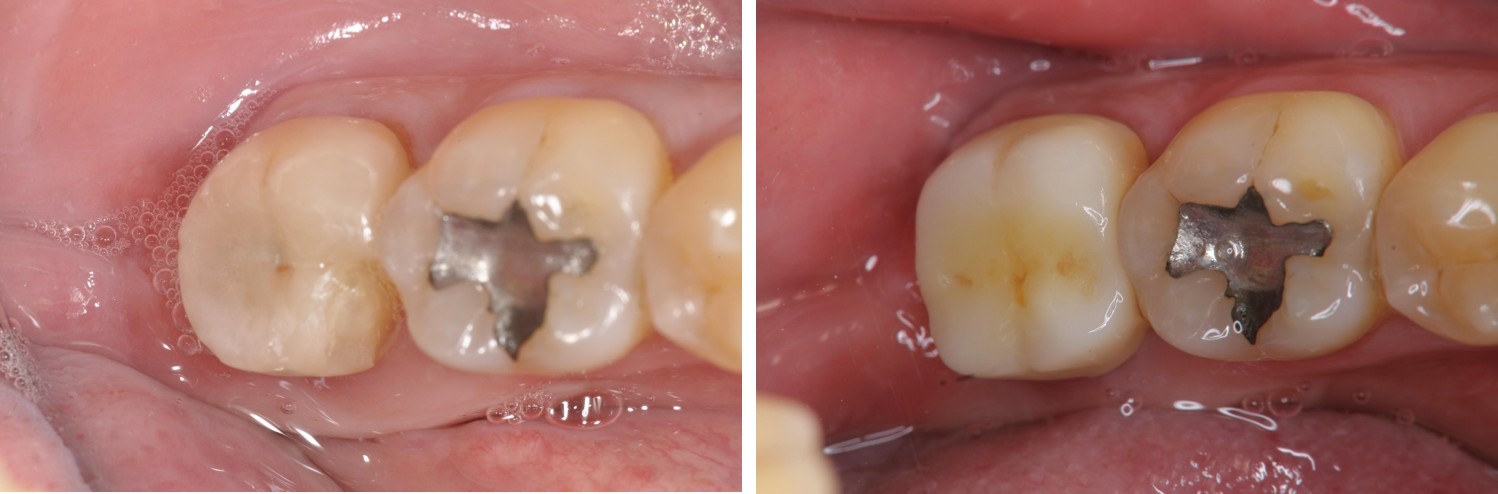

治療後,咬合良好

術前、術後比較